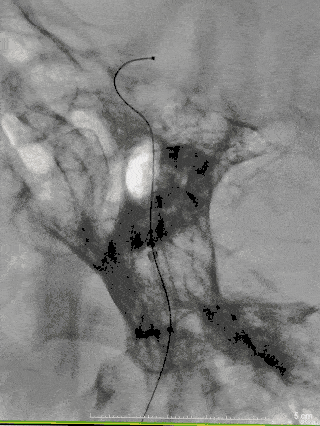

术后造影

术后即可造影可见造影剂滞留,术后顺利复苏,无不适,术后5天出院。

图7

术后三个月返院复查提示血管进一步修复,造影剂滞留明显。

图8